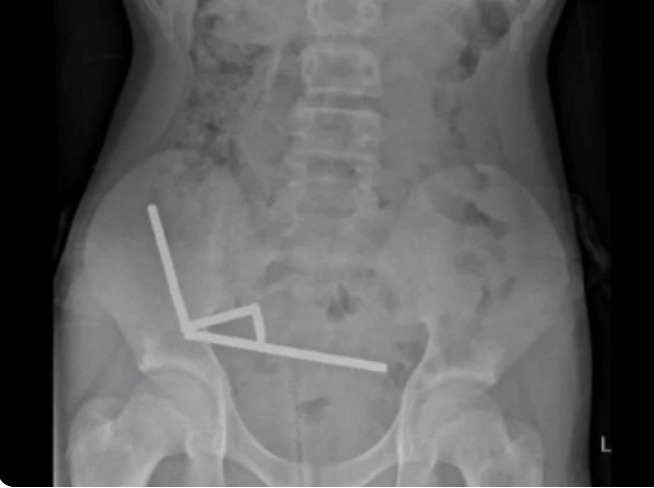

Ele foi internado após quatro dias de dores abdominais e exames de imagem mostraram correntes de ímãs aderidas entre diferentes partes do intestino, unidas pela força magnética. O contato prolongado causou necrose por pressão e risco de perfuração intestinal.

Durante a cirurgia, os médicos encontraram quatro áreas necrosadas e precisaram remover parte do intestino para retirar todos os ímãs. Após oito dias de internação e tratamento de complicações leves, o paciente recebeu alta. O hospital onde o procedimento foi realizado não foi divulgado.